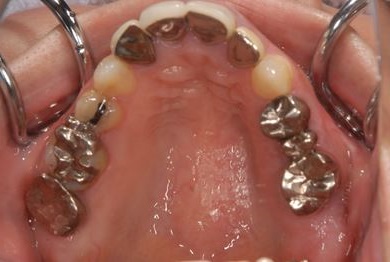

| 性別/年齢 | 女性 / 38歳 | ||||||||||||||||||||||||||||||||

| 主訴 | 奥歯の痛み(虫歯)。銀歯の所だと思います。なるべく痛くない治療がいいです。 | ||||||||||||||||||||||||||||||||

| 治療方針 | セラミック治療にて、審美的回復を行う。 | ||||||||||||||||||||||||||||||||

| 治療内容 | ハイブリッドセラミッククラウン1本(ハイブリッドセラミック用土台1本) | ||||||||||||||||||||||||||||||||

| 総治療費 | 96,600円 | ||||||||||||||||||||||||||||||||

| 治療期間 | 2ヶ月 |